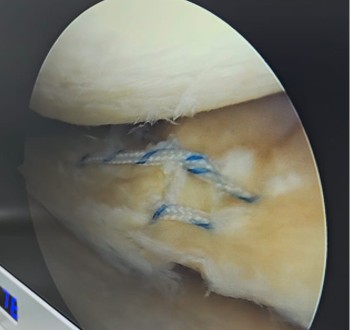

Las lesiones meniscales son la patología más frecuente en la rodilla con una incidencia anual de 66 por cada 100,000 habitantes1. Los meniscos son estructuras fibrocartilaginosas localizadas entre los cóndilos femorales y platillo tibial, permiten el impacto de cargas, estabilidad y lubricación de la rodilla. Estas estructuras tienen una composición compleja y organizada que permiten la conversión de fuerzas axiales compresivas en circunferenciales que previenen extrusión y ruptura, así como fibras radiales que evitan su ruptura longitudinal.